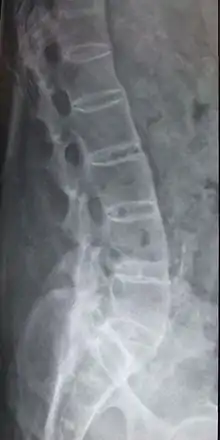

Radiographie latérale du rachis mettant en évidence une spondylarthrite ankylosante

Le diagnostic de cette maladie repose sur un ensemble d'éléments dont :

Les radiographies du bassin permettent de visualiser un contour estompé de l'articulation sacro-iliaque, voire un élargissement de la jonction. À un stade plus avancé, elles mettent en évidence des érosions ou des ossifications aux endroits où s’insèrent les enthèses. Parfois, la colonne vertébrale paraît complètement ossifiée et fusionnée avec l'aspect de « tronc de bambou » dans les formes évoluées.